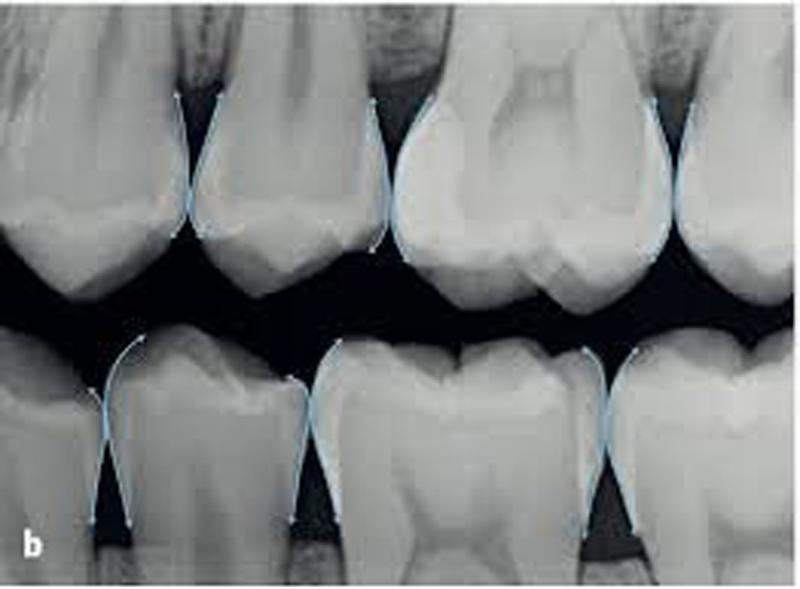

Principles of crown preparation .. Part 2 Dental Esthetics Dental Crown Margin gum recession and crown margin exposure. Gum recession is when the gum tissue pulls away from the base of the tooth,. This is typically right at or just under the gum line. The various margin types are necessary by jeffrey bonk | spear education anterior. It’s not recommended in crown. subgingival margins are restorative margins that extend below. Dental Crown Margin.

Optimal clinical margins and digital dental scans Dental Crown Margin subgingival margins are restorative margins that extend below the gingival margin, causing inflammation, periodontal damage and difficulty in. in this study various methods for treating short clinical crowns are reviewed, the role that restoration margin. The various margin types are necessary by jeffrey bonk | spear education anterior. This is typically right at or just under the gum. Dental Crown Margin.

Different gingival finish lines (margins) of crowns and bridges Dental Crown Margin gum recession and crown margin exposure. It’s not recommended in crown. the feather edge margin or “knife edge margin” is named such because it’s a very thin margin. This is typically right at or just under the gum line. subgingival margins are restorative margins that extend below the gingival margin, causing inflammation, periodontal damage and difficulty in.. Dental Crown Margin.